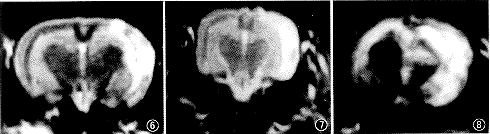

缺血组40只兔缺血2小时T2WI均为阴性,4小时19只出现稍高信号改变,6小时28只出现稍高信号改变,24小时存活30只均出现缺血区高信号改变。48、72小时MR T2WI梗死区大小、信号强度与24小时表现相同。健侧及对照组无此改变。根据24小时MR T2WI所确定的梗死灶位置将30只存活兔分为3型:半球型,13只,发生率44%;基底节和(或)小叶皮层型,10只,发生率33%;局灶型,7只,发生率23%(图6~8)。

图6~8 兔脑梗死MR分类。图6为Ⅰ型(左侧大脑半球见明显高信号梗死区);图7为Ⅱ型(左侧皮层见明显高信号梗死区);图8为Ⅲ型(左侧皮层见散在高信号梗死区)